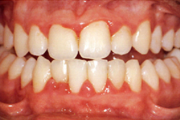

Gingiviit ehk igemepõletik